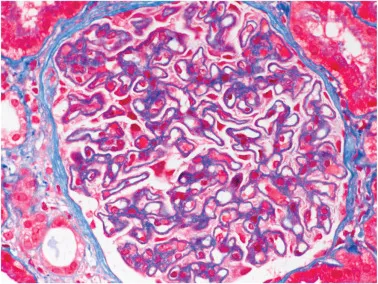

Meu paciente com NIgA tem proteinúria entre 0,5–1,0 g/dia, já está em iECA e iSGLT2: devo pensar em imunossupressão?

Proteinúria entre 0,5–1,0 g/dia na NIgA não é benigna e já se associa a maior risco de progressão renal. A evidência atual reforça <0,5 g/dia como alvo terapêutico, valorizando proteinúria cumulativa e tendência ao longo do tempo. Antes de pensar em imunossupressão, o foco deve ser otimização máxima da terapia de suporte e estratificação cuidadosa de risco.